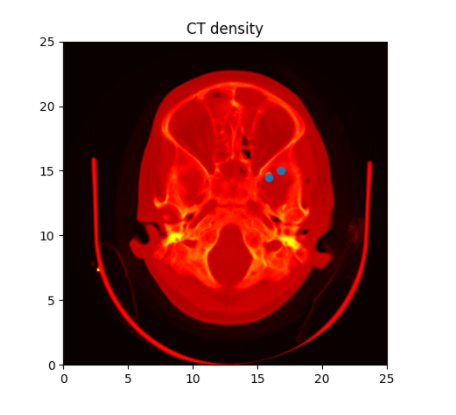

Data & Data Structure

- MRI brain images (volumetric representation)

- NIfTI (.nii) files

- Size: 17.3 GB

- 1113 samples (brains)

- Preprocessed version of data

- Skull stripping.

- Normalized.

The human connectome project, 1113 subjects’ brain T1w structural images. These 3D MPRAGE (this sounds nice) images obtained from Siemens 3T platforms using a 32-channel head coil.

Data exploration

Cropping

cropped = data[50:205,60:225,30:225] #155x165x195

data = img.get_data() #256x256x256

Resize

(155, 165, 195) array #4987125 voxels (50, 50, 50) array #125000 voxels

resampled = zoom(cropped, (50/cropped.shape[0], 50/cropped.shape[1] , 50/cropped.shape[2])